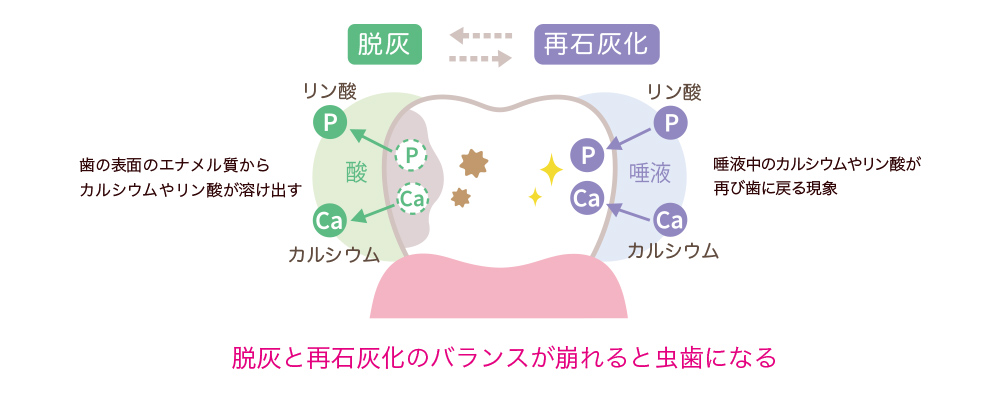

歯の表面のエナメル質はとても硬い組織ですが、酸にさらされる時間が長くなると徐々に溶けていきます。これを「脱灰」といいます。一方で、唾液の働きによって溶けかけた歯を修復する作用もあります。これが「再石灰化」です。本来は、唾液に含まれるカルシウムやリン酸(ミネラル)によって再石灰化が促され自然修復されますが、だらだら食べや清掃不良など、糖分が口に残っている状態が続くとミュータンス菌が出す酸によって脱灰が起こりやすくなります。

虫歯予防に欠かせない「脱灰」と「再石灰化」のバランス

虫歯予防には、「脱灰」と「再石灰化」のバランスが非常に重要です。脱灰(だっかい)と再石灰化は、食事のたびに歯の表面で起こる自然な均衡メカニズムです。通常私たちの口腔内は、唾液によって中性に保たれていますがダラダラ食べをしている、歯みがきが不十分といった生活習慣は、脱灰が優位な時間を長くしてしまいます。脱灰と再石灰化のバランスが「脱灰」に傾いた時に虫歯が進行してしまいます。